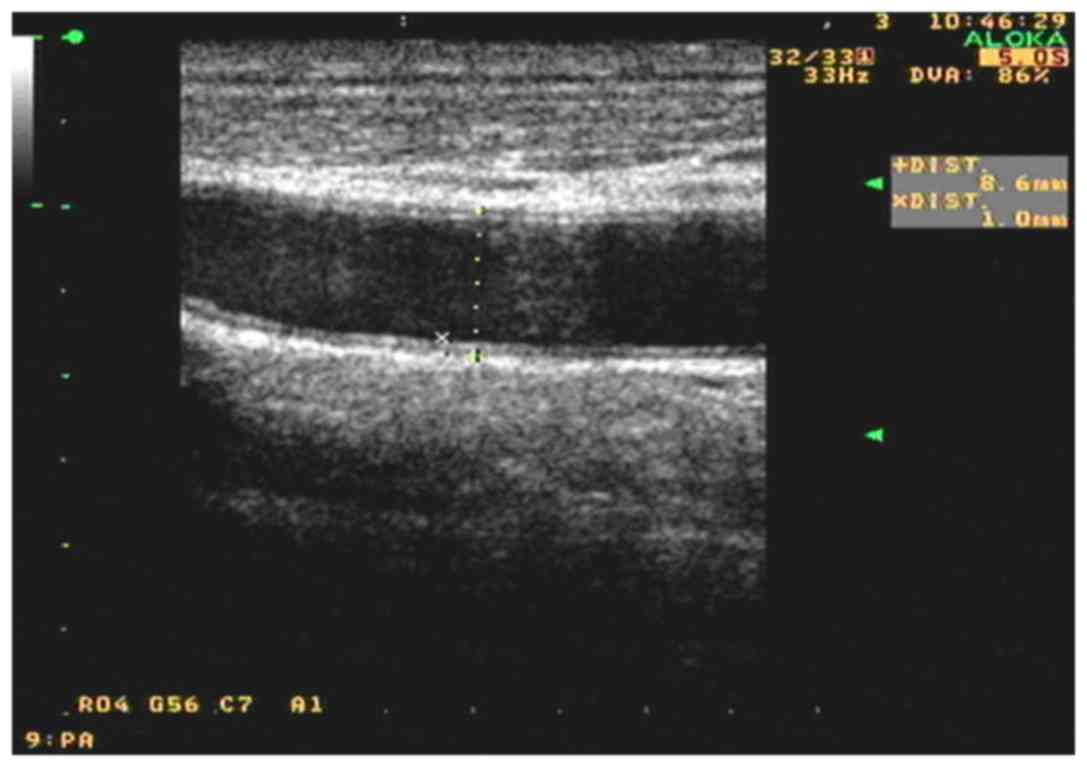

Ultrasound examination and IMT quantification

All measurements of carotid artery IMT were performed as part of a routine examination by the same technician, who was blinded to the subjects' clinical data. High-resolution B-mode carotid ultrasonography was performed using an 8–12 MHz transducer and an Aloka SSD-5500 ultrasound scanner (Aloka, Andover, Japan). The patients lied in the supine position with the head slightly tilted to either side at examination. Wall changes were carefully identified in the carotid arteries from different longitudinal and transverse views. The images were focused on the far wall of the artery. In all subjects, the common carotid artery, the internal and external carotid arteries and the carotid bulb were examined. Subsequent to identification of a region ~1.0 cm proximal to the carotid bifurcation, the IMT of the far wall was evaluated as the distance between the luminal-intimal interface and the medial-adventitial interface, measured thrice, and the average IMT value was used. Based on the data in healthy Chinese subjects, abnormal IMT was defined as an IMT of >1.0 mm.

Carotid artery IMT

The IMTs are shown in Table II. After 12 weeks of allicin administration, the carotid artery IMT in the allicin group was significantly decreased compared with that in the control group (1.13±0.10 vs. 1.23±0.08 µmol/l; P<0.05). Compared with the baseline value, the IMT was significantly decreased after allicin treatment (P<0.01). The IMT was also significantly decreased in the control group (P<0.05), but that the decrease was greater in the allicin group (P<0.01). As shown in Figs. 1 and 2, after allicin treatment, the IMT was decreased from 1.4 to 1.0 mm.

Figure 1.

Carotid artery high resolution color Doppler ultrasonograph of a selected frame of a typical case prior to treatment.

Figure 2.

Carotid artery high resolution color Doppler ultrasonograph of a selected frame after allicin treatment of the same typical case as in Fig. 1.